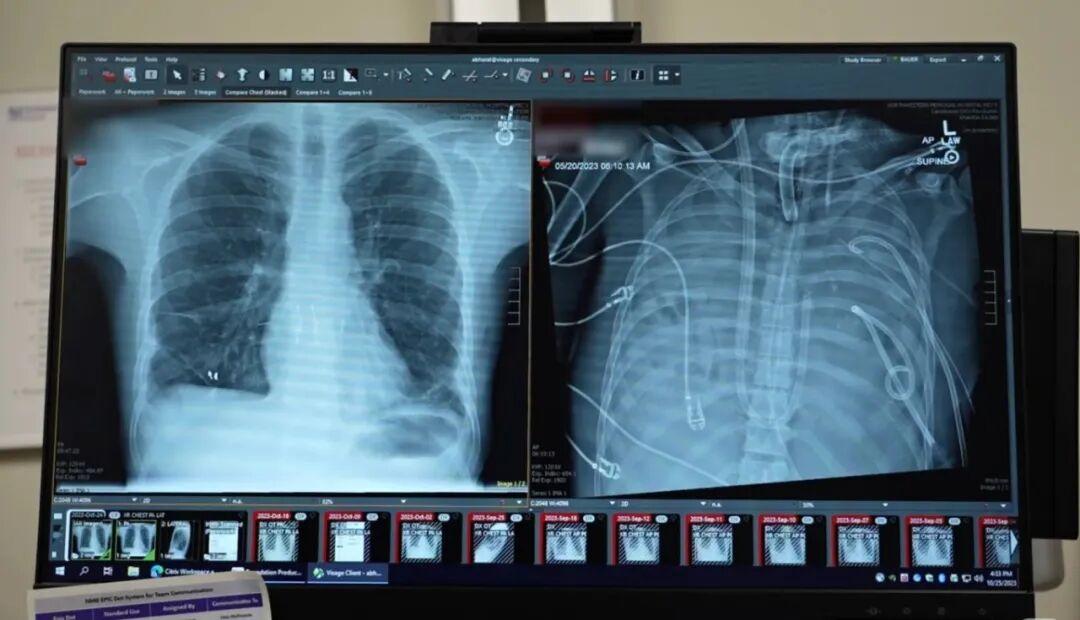

一场普通流感,竟让年轻男子双肺彻底坏死、多次心脏骤停,常规治疗早已无力回天,医生甚至断言他撑不过几天。就在生死边缘,一支顶尖医疗团队做出大胆决定:摘除全部坏掉的双肺,靠一套人工系统维持生命,等待供肺移植。

这堪称医学史上的奇迹——男子在完全没有肺的状态下,平稳撑过关键窗口期,顺利完成移植,术后多年恢复良好,生活完全自理。更值得关注的是,这场突破性手术,有华人医生深度参与并担任核心执笔,为这项创举注入了中国智慧。

很多人好奇,没有肺该如何呼吸循环?团队到底用了什么精妙设计,解决了心脏压力失衡、血液凝固等致命难题?普通流感为何会恶化到如此地步,这项技术又能给多少重症患者带来生机?这些硬核细节远比听起来更震撼。